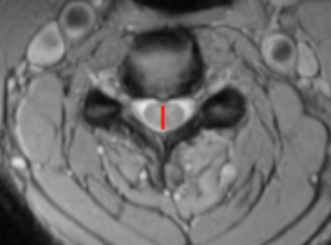

Image Type Cervical Spine X-Ray CT Scan MRI Scan Compression Ratio (AP diameter transverse diameter of cord) Cord Cross-Sectional Area (CSA) Cross-Sectional Canal Area Maximum Spinal Cord Compression Pavlov/Torg (Canal-Body Ratio) Sagittal Canal Diameter Spinal Cord Signal Change - T1 Hypointensity Spinal Cord Signal Change - T2 Hyperintensity (+ number of levels)